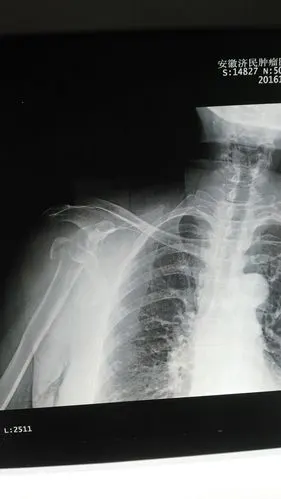

我院完成肩关节置换手术